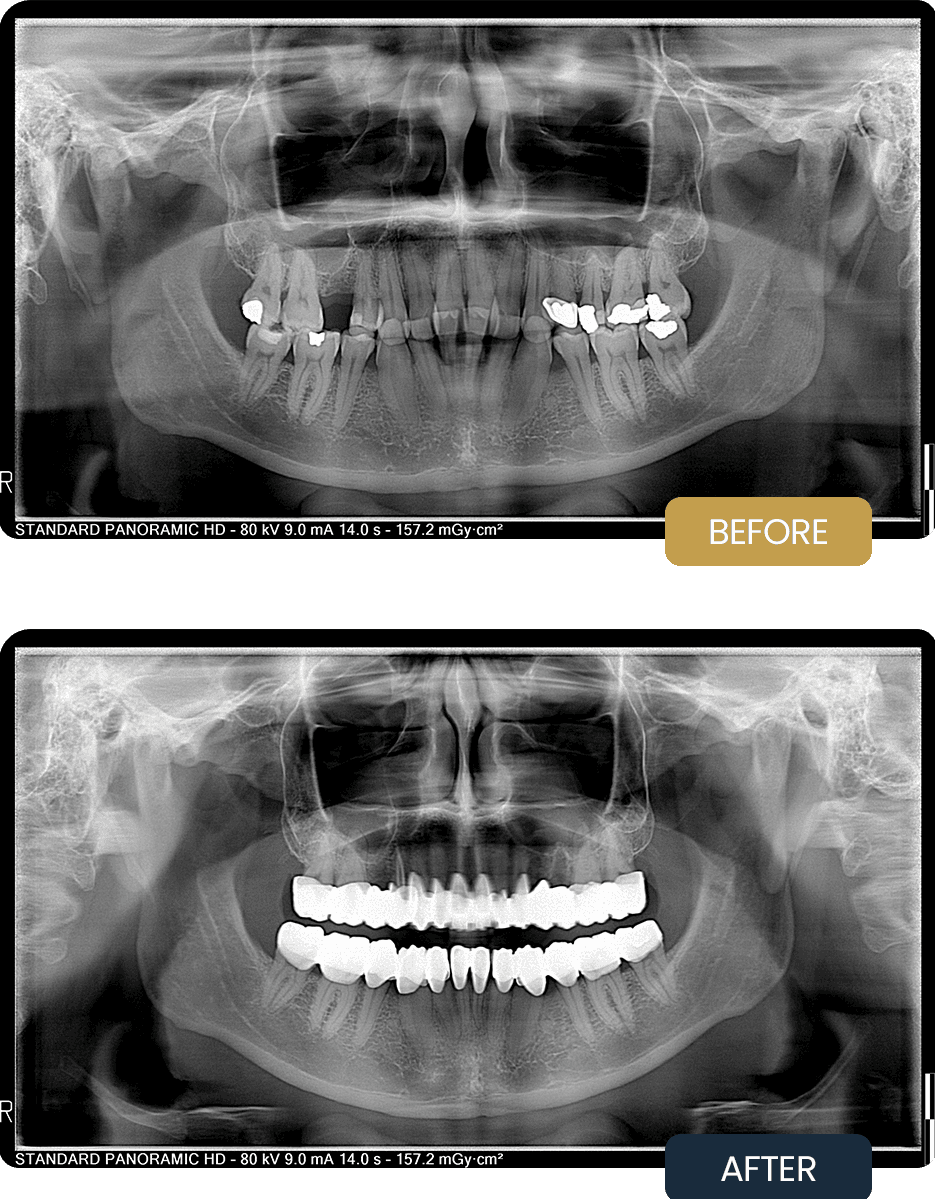

Panoramic imaging confirmed the need for endodontic treatment on selected teeth, restorative reinforcement, and full coverage crown rehabilitation to restore strength, function, and long term predictability.

Post treatment panoramic imaging confirmed successfully treated root canal teeth, stable restorations, and accurately seated zirconium crowns.

The final restorations restored proper bite alignment, improved chewing comfort, and delivered a natural looking, harmonious smile with long term stability.